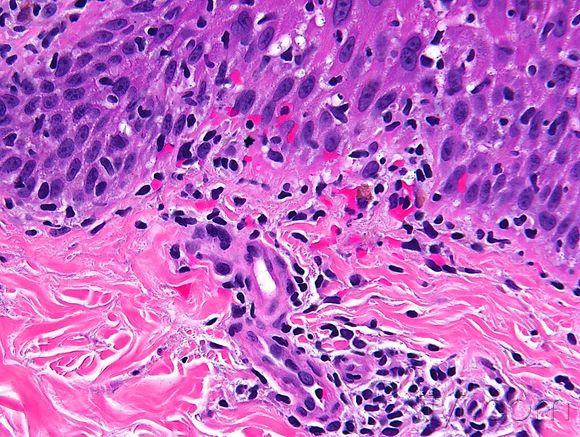

皮肤临床病理06线状苔藓